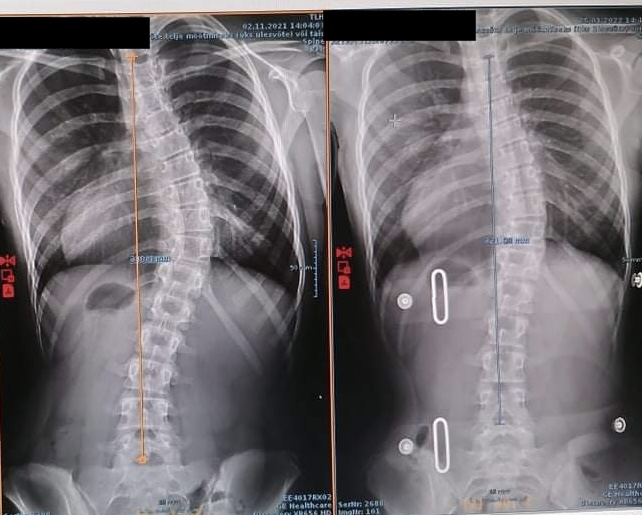

Lõpetuseks tore “enne ja pärast” pilt minu patsiendist, kes kasutas skolioosikorsetti ning skolioosispetsiifilist füsioteraapiat oma idiopaatilise skolioosi ravis.

Heaks korrektsiooniks loetakse vähemalt 50% Cobb nurkade vähenemist, kui korsett on seljas. Olenevalt nooruki vanusest, kasvamisest, ravi efektiivsusest jne on vajalik korsetti uuendada, et tagada maksimaalne raviefekt.